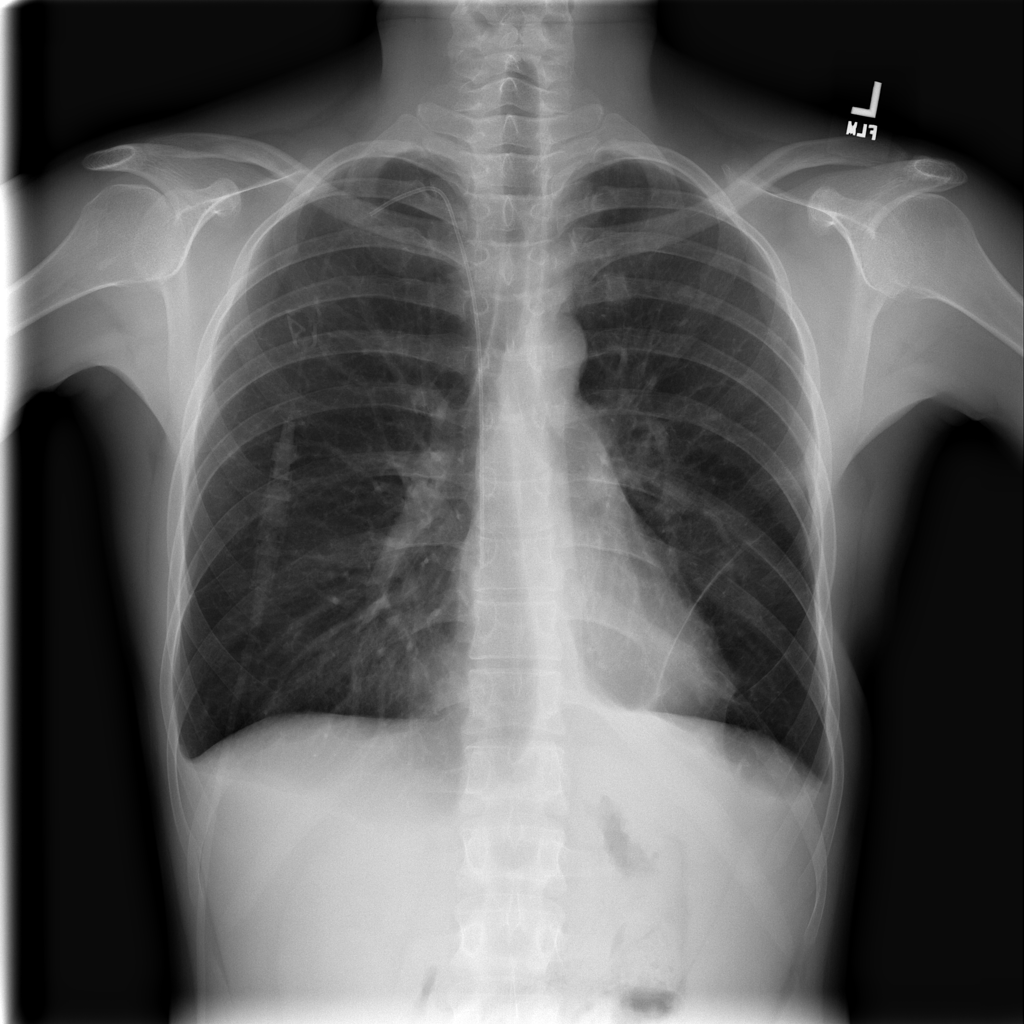

Showing up to 90 reference images for Nodule.

PAT-FB8F · IMG-000Nodule

PAT-FB8F · IMG-000

PA